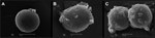

Scanning electron microscopy (SEM) showed that the nicotine-treated oocytes appeared nonspherical with rough surface and the zona pellucida (zp) was torn and became irregular. Supplementation with gamma-tocotrienol in the nicotine-treated mice retained the spherical shape of the oocytes with intact zp; however, the surfaces of the oocytes remained irregular and rough. Transmission electron microscopy (TEM) following chronic nicotine treatment showed loosening of the boundary and tearing of the zp. The perivitelline space was also widened. The cytoplasm of the oocytes retained abundant rough endoplasmic reticulum (rER) with numerous vesicles. Mitochondria were highly dense, with no cristae. The administration of gamma-tocotrienol partially reduced the detrimental effects of nicotine by retaining the smooth boundary of the zp with the tight perivitelline space. There was less rER with no visible vesicle and a lower amount of dense mitochondrial matrix.